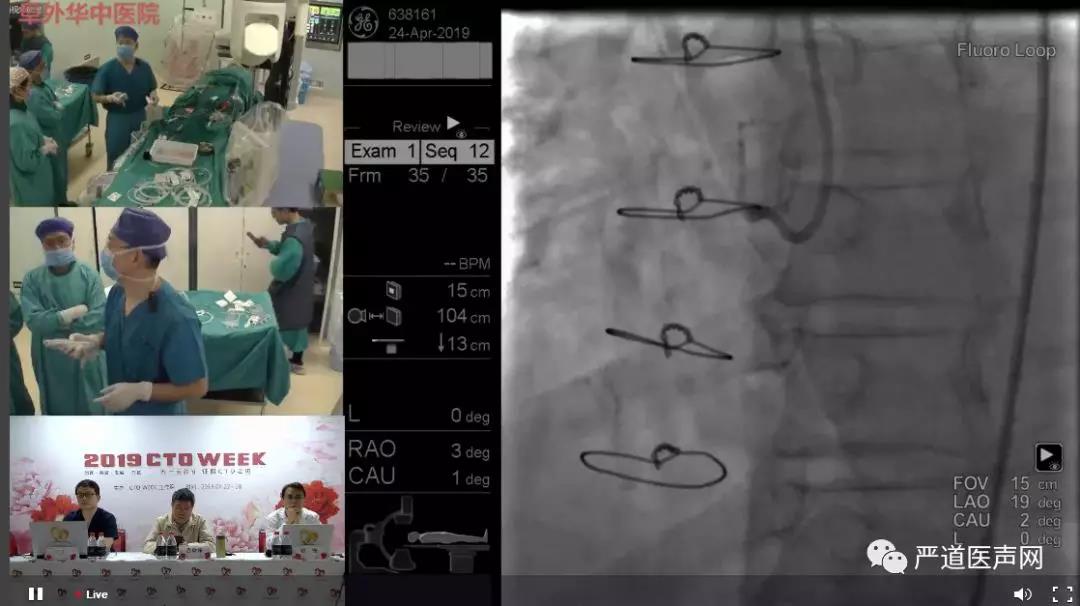

2019年4月24日,2019 CTO WEEK进入第三天。首都医科大学附属北京安贞医院、华盛顿大学医学中心(University of Washington Medical Center)、英国Belfast医学中心(Belfast Medical Center, Belfast, United Kingdom)、沧州市中心医院、阜外华中心血管病医院和空军军医大学西京医院等6个中心在4个演播室带来8场手术演示,步步惊心,扣人心弦。

华盛顿大学医学中心William L. Lombardi教授带领团队演示了一例桥血管+支架+长段钙化闭塞的病例。经过仔细分析研讨,William L. Lombardi教授选择通过桥血管做逆向CTO,手术非常成功。特别值得一提的是,最后用机器人完成了IVUS指导下支架的植入,让人大开眼界。

下午,第一演播室由欧洲心脏病学会委员、英国Belfast医学中心心内科Simon James Walsh教授进行手术演示。Simon James Walsh教授是世界著名的冠心病介入治疗专家,他应用世界先进的ADR技术较大地提高CTO手术成功率,同时缩短手术时间、减少造影剂用量及造影剂相关性肾病等手术并发症的发生率。手术前半段Simon James Walsh教授一直尝试用正向技术进行打通,但右冠中段比预想要严重,走行方向不是很理想,最后决定转换策略进行逆向介入。

在第三演播室,上午沧州市中心医院徐泽升教授和高雄长庚医院心脏内科主任郑正一教授携手进行演示手术,北京中日友好医院杨鹏教授作《AMI合并CTO的处理原则及注意事项》的主题报告。下午,阜外华中心血管病医院高传玉教授、陈岩教授,广东省人民医院张斌教授三位专家联合进行了手术演示,北京安贞医院郑泽教授作《CTO合并钙化病变的处理 》主题报告。